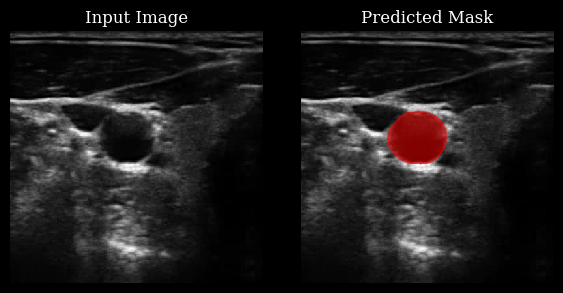

Carotid artery segmentation¶

This section demonstrates how to use the CarotidSegmenter

model from the zea

library to segment the carotid artery in ultrasound images. The model predicts a mask highlighting the carotid region for a given input image.

For more details, see the original paper:

Luuk van Knippenberg, “Unsupervised domain adaptation method for segmenting cross-sectional CCA images”, Computers in Biology and Medicine, 2022.

for ax_img, ax_mask, img_arr, mask_arr in zip(axes[:, 0], axes[:, 1], batch[..., 0], masks_clipped):

ax_img.imshow(img_arr, cmap="gray", vmin=0, vmax=1)

ax_img.set_title("Input Image")

ax_mask.imshow(img_arr, cmap="gray", vmin=0, vmax=1)

add_shape_from_mask(ax_mask, mask_arr, color="red", alpha=0.5)

ax_mask.set_title("Predicted Mask")